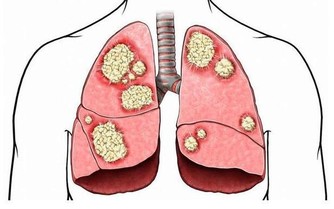

直腸癌患者的大便帶血,是因為腫瘤本身表面破潰,不斷地出血或滲血,而大便在直腸儲存時,會與血液混合,造成大便內混雜血液。因此表現為大便本身帶粘液,血液顏色多為暗紅色或者果醬色,甚至黑色

直腸癌作為腫瘤,位置固定,質地較硬,會導致直腸壁僵硬、受壓,從而出現大便次數增多,排便後不久又出現便意,但無糞便或者少量糞便排出。

如果進一步發展,還會導致大便困難、大便變細等,少數患者還會因直腸梗出現腹痛、腹脹等症狀。